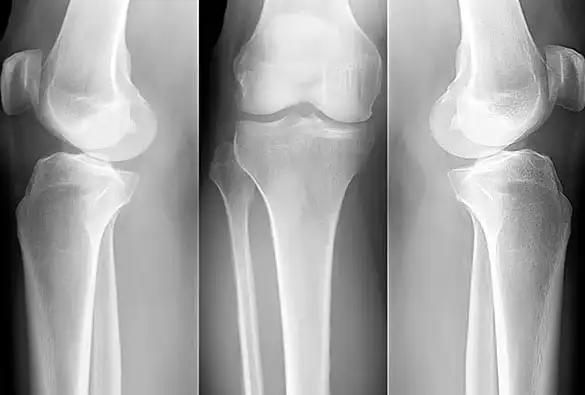

Bone Density Testing

The gold standard for diagnosing osteoporosis is a bone density test, usually performed using dual-energy X-ray absorptiometry (DXA). DXA scans measure bone mineral density (BMD) at specific sites, such as the hip and spine. The results are compared to the average BMD of a young, healthy adult of the same sex, resulting in T-scores. A T-score of -2.5 or lower at the hip or spine indicates osteoporosis, while a T-score between -1.0 and -2.5 indicates osteopenia, a precursor to osteoporosis.

Additional Tests

In some cases, additional tests may be recommended to evaluate underlying causes of osteoporosis or assess fracture risk. These may include blood tests to measure levels of calcium, vitamin D, hormones (such as estrogen or testosterone), and markers of bone turnover. Other imaging tests, such as X-rays or vertebral fracture assessments (VFAs), may be performed to identify existing fractures or assess spinal deformities.